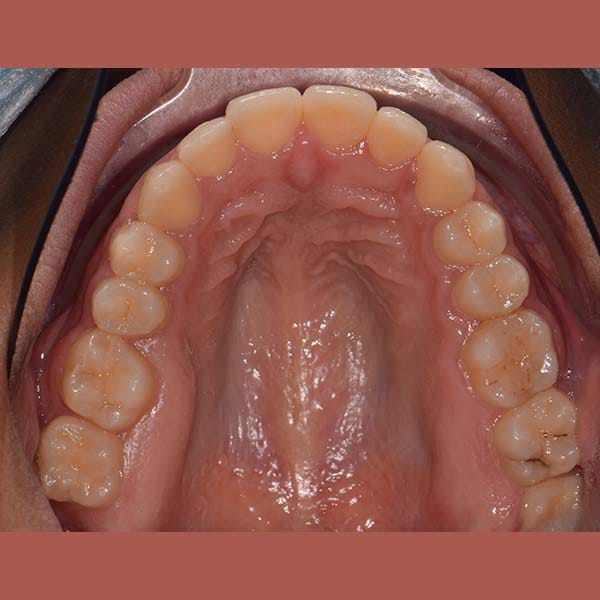

AFTER

The teeth overlay was treated orthodontically by means of fixed braces and without any tooth extraction. We also pulled the posterior molars forward to close the gap successfully, and the gummy smile was almost solved without the need for surgery.